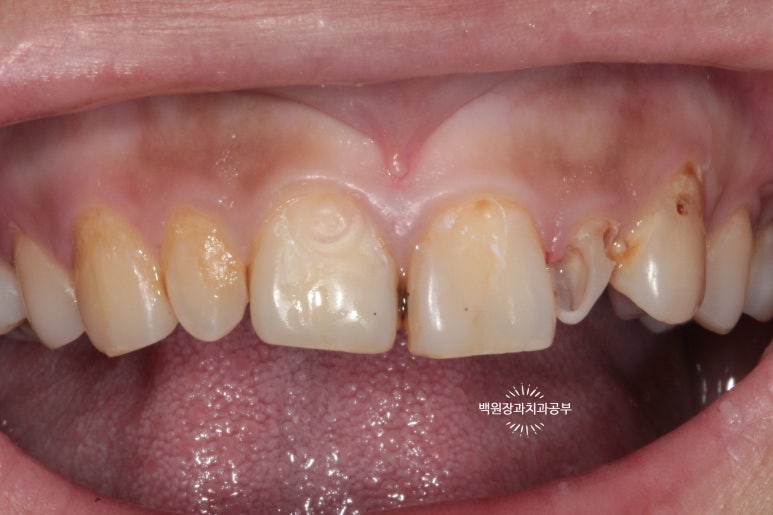

저희 병원을 처음 내원하셨을 때의 구내 임상사진입니다.

20대 여성분이셨는데, 개인 사정으로 적절한 내원 타이밍을 놓쳐 대문니(=중절치)를 비롯하여 상당히 충치가 진행된 양상을 띄고 있습니다. 특히 대문이 옆의 작은 앞니(=측절치)는 충치가 더 심했습니다.

고개를 살짝 돌려 찍어본 사진에서 더 확연히 치아우식증( =충치)을 확인 할 수 있습니다.

딱 보기에도 치료가 아주 시급해 보이는 상황이었어요!!

그리고 화살표로 표시한 양쪽 작은 앞니는 왜소치로 그 크기가 2/3 정도로 작은 소견을 보실 수 있습니다.

환자분은 당시에 흡연 하시는 상태였는데요, 그로 인해 치은염 (=잇몸 염증)도 심하여 꽤나 잇몸이 부어있는 것을 확인할 수 있었습니다.

화살표로 표시해 둔 치아와 치아 사이의 잇몸이 상당히 붉고, 붓기로 인해 모양이 둥그렇게 변한 것을 보실 수 있습니다. 전형적인 치은염/치주염 소견입니다. 심해지면 풍치가 됩니다.